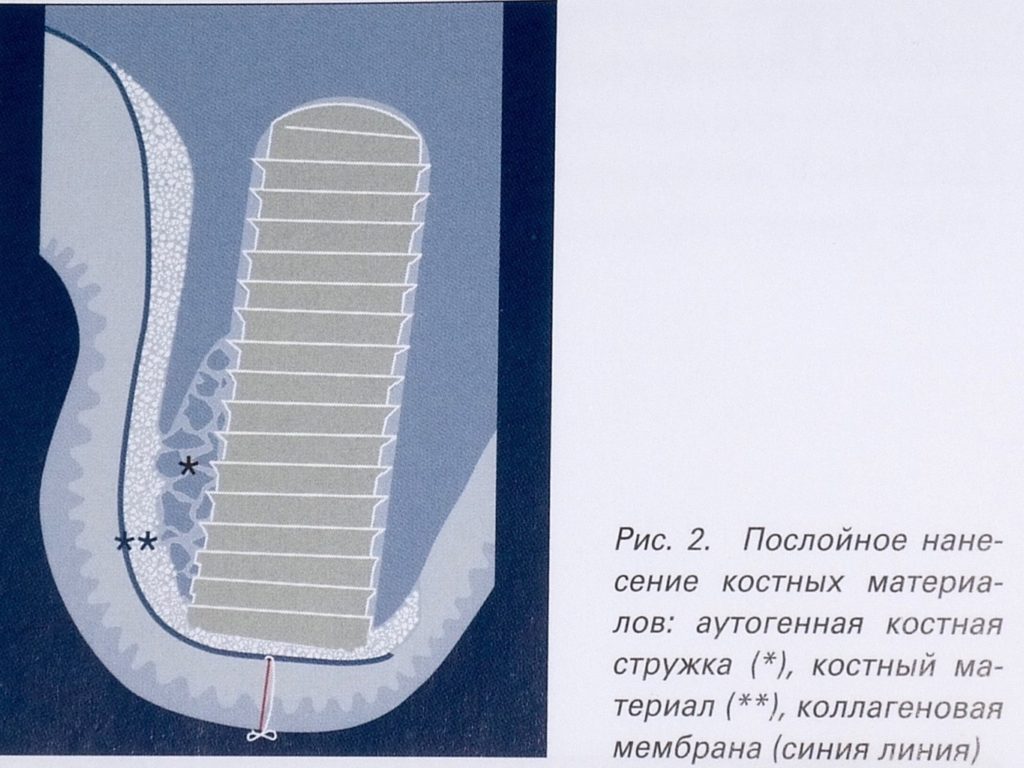

Принцип направленной костной регенерации. Костная регенерация под защитой мембраны Биоматрикс

Принцип направленной костной регенерации. Костная регенерация под защитой мембраны Биоматрикс

Принцип направленной костной регенерации. Костная регенерация под защитой мембраны Биоматрикс